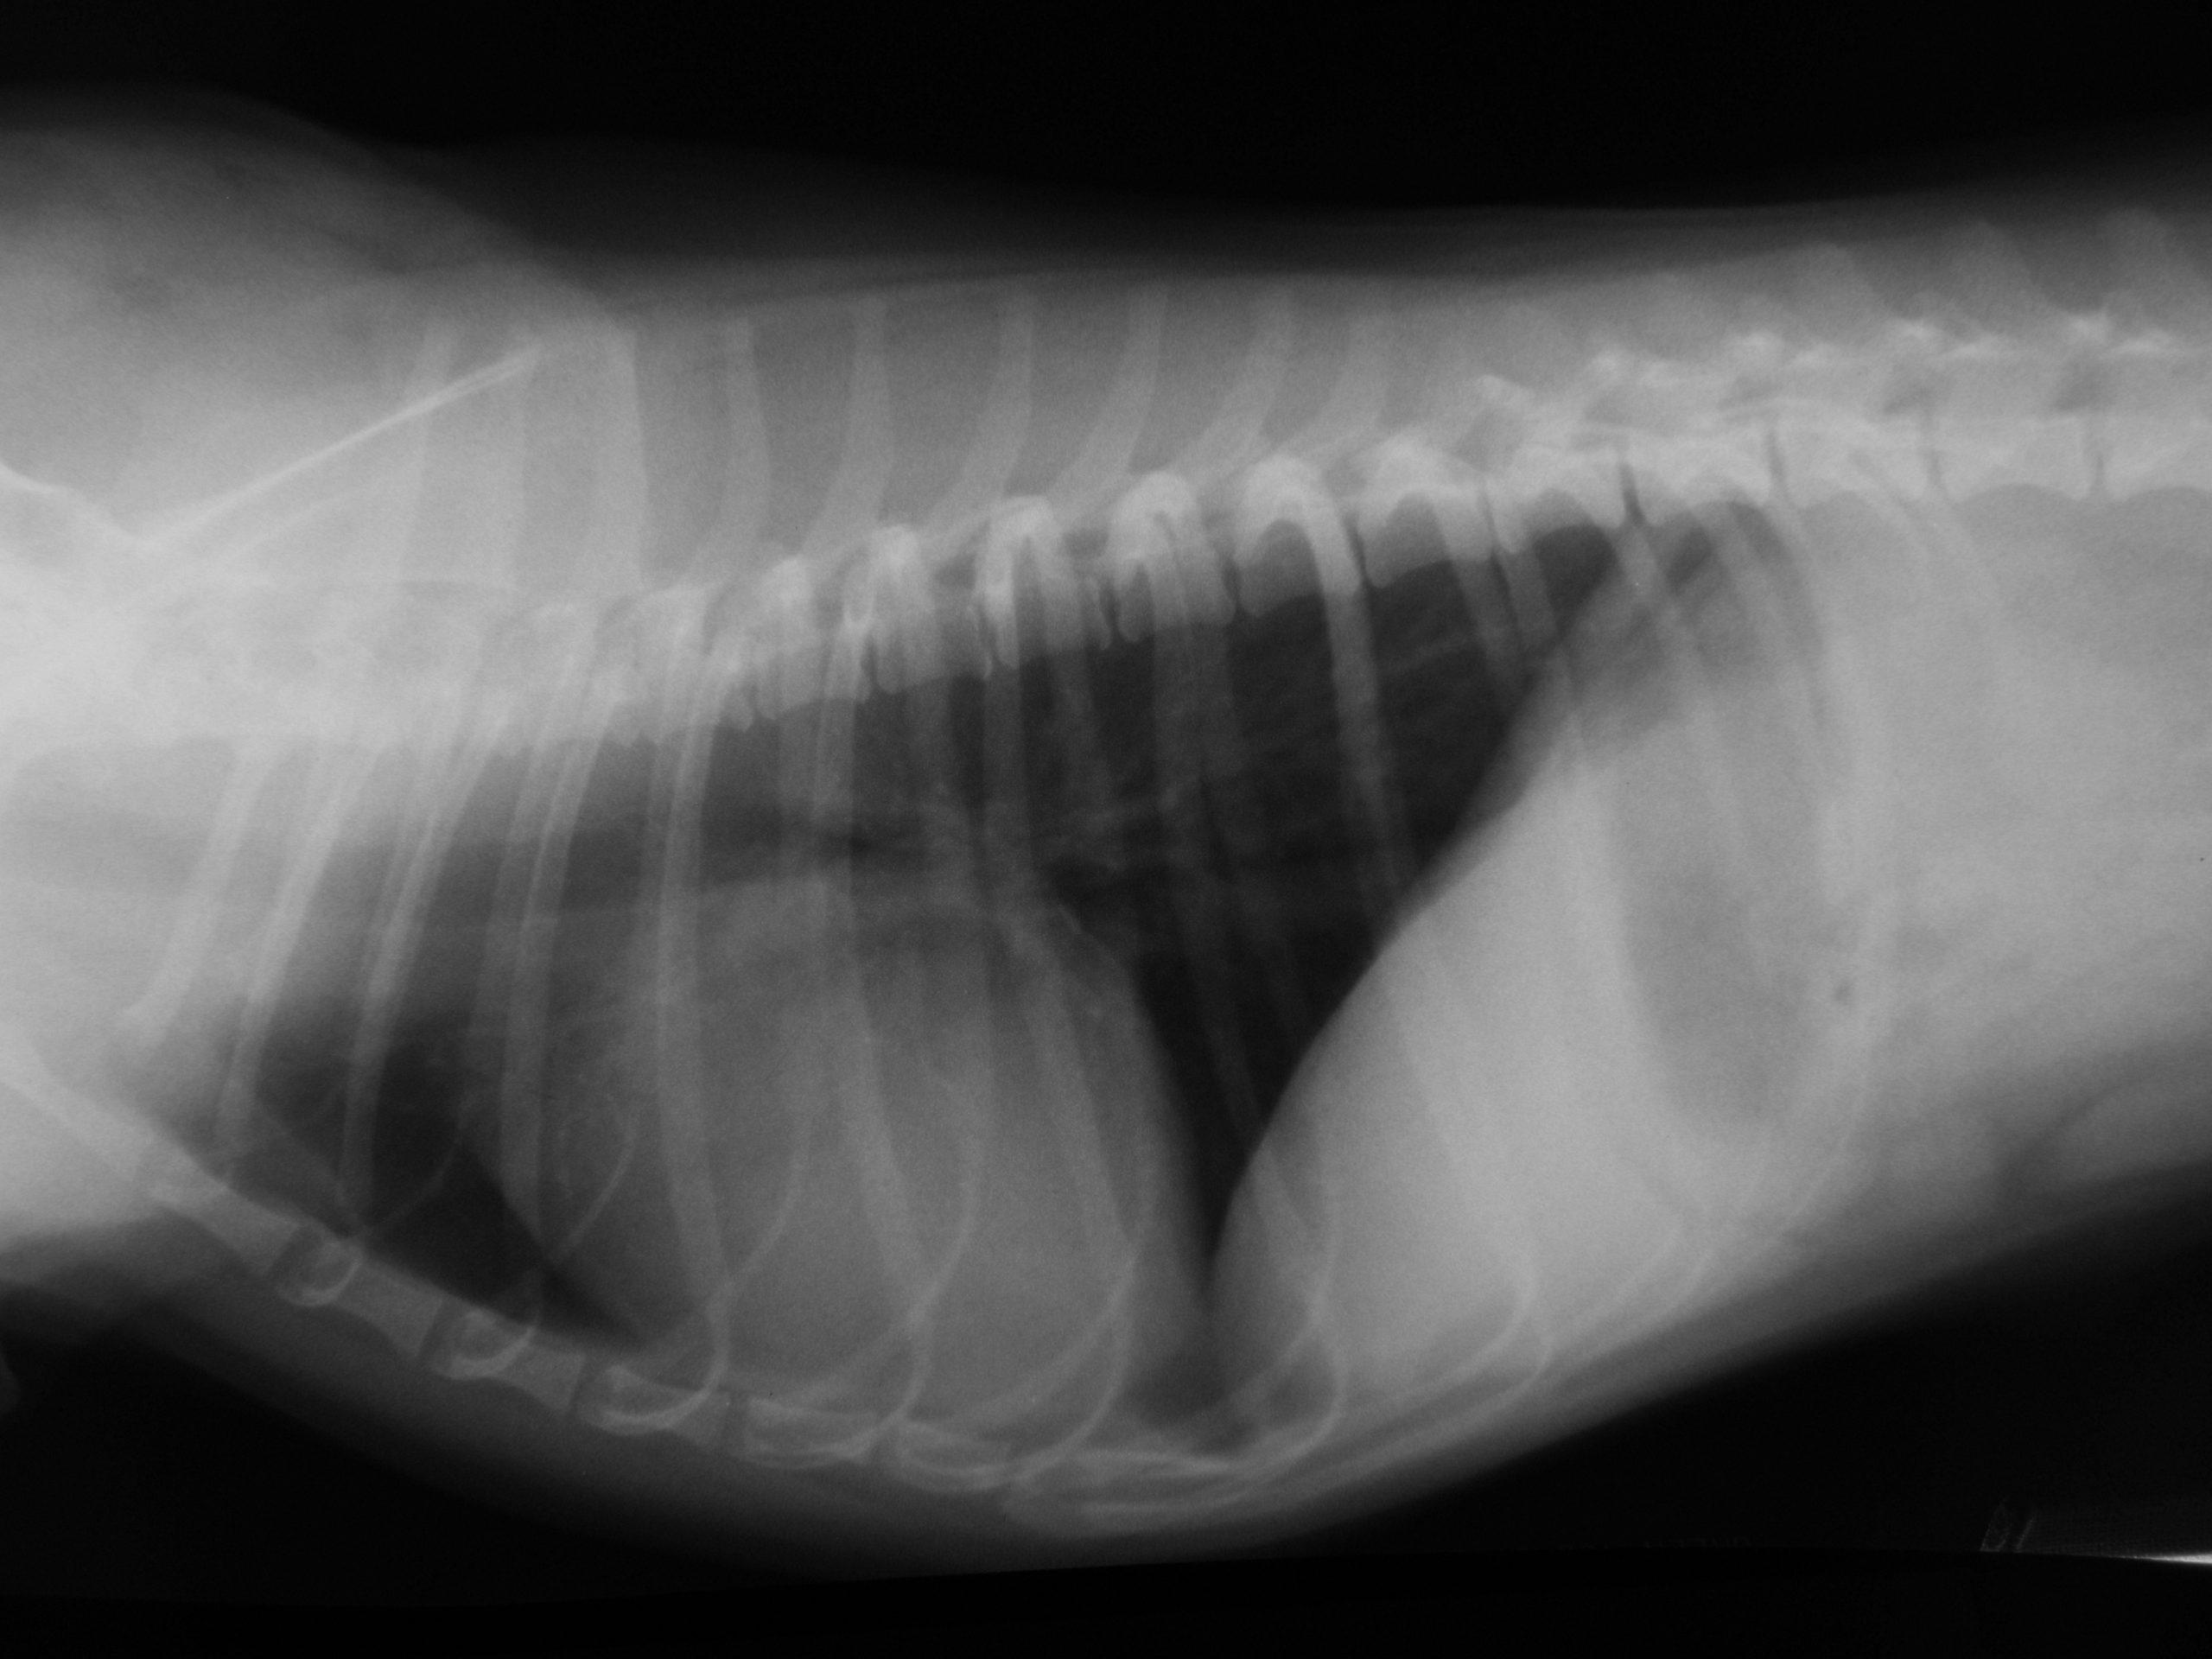

See this reverse VSD with bubble study performed by Dr. Doug Casey of Vancouver B.C. Canada. English Bay Ultrasound.